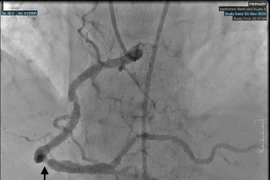

Ngay khi tiếp nhận, các bác sĩ đã tiến hành siêu âm và chụp chiếu, phát hiện khối phình động mạch chủ bụng rất lớn và có những vị trí nghi ngờ đã vỡ. Các bác sĩ chẩn đoán người bệnh bị vỡ phình động mạch chủ bụng sau phúc mạc và chỉ định phẫu thuật khẩn cấp do sốc mất máu.

Dưới sự chỉ huy của TS.BS Nguyễn Công Hựu, Giám đốc Bệnh viện E, các bác sĩ khoa Phẫu thuật tim mạch và lồng ngực đã tiến hành phẫu thuật cho người bệnh. Trong ổ bụng có nhiều dịch màu đen, sau phúc mạc quanh động mạch chủ chậu có khối máu tụ rất lớn.

Các phẫu thuật viên tiến hành mở khối phồng động mạch chủ, xung quanh có rất nhiều máu và máu tụ, trong lòng khối phồng có nhiều máu cục đã tổ chức hóa và xơ vữa bám thành, thành bên trái có vết rách kích thước 0,5cm. Các phẫu thuật viên đã cắt bỏ đoạn động mạch bị phình vỡ và thay thế bằng mạch máu nhân tạo.